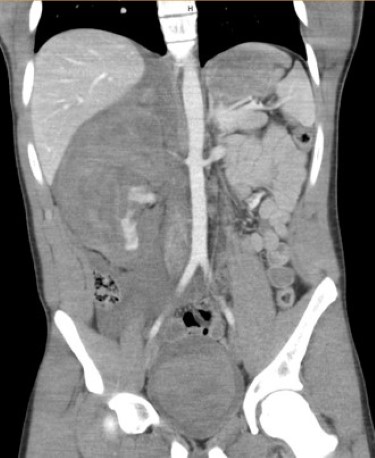

A 16-year-old male presents with acute hematuria and abdominal pain after being checked with a lacrosse stick during practice. He is hemodynamically stable with a heart rate of 58. A FAST exam is performed by the treating clinician within 15 minutes of arrival to the pediatric emergency department. On FAST examination, there is free fluid in the right upper quadrant, and a mass is visible at the edge of the liver where the kidney is expected to be seen (Video 7). On the suprapubic view, the bladder contains a large echogenic clot (Video 8). Immediate surgical consultation and a CT scan confirm the presence of a large retroperitoneal hematoma with extravasation (Figure 3). The patient requires urgent operative intervention and nephrectomy.

Figure 3

Case 4 emphasizes the FAST exam's ability to detect complex injuries, such as a retroperitoneal hematoma and a bladder clot, leading to life-saving surgical treatment.